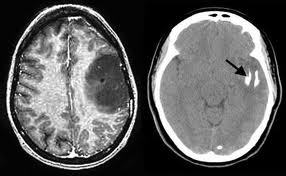

Tumor detection

MRI CT-SCAN

Brain imaging techniques

- Computerized tomography (CT) scan– uses X-rays in 3-dimensions to generate a brain image

- Can be digitally sectioned to show internal areas of the brain

- Can distinguish between grey matter and white matter, see the ventricles, has resolution of several millimeters

Magnetic resonance imaging (MRI)

- Uses rotating magnets to generate image

- Non-invasive

- Can view images from any angle

- Resolution under 1 mm